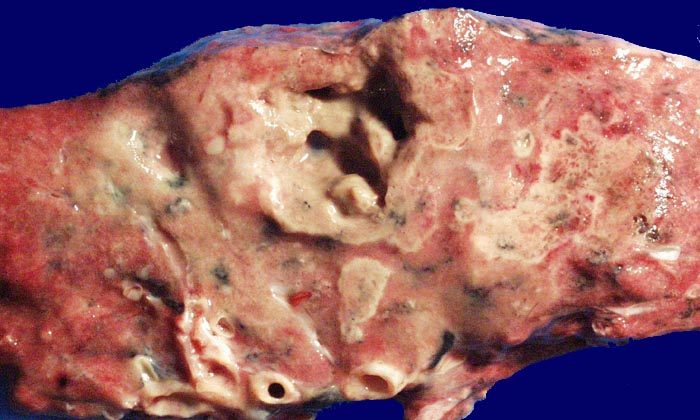

Pilzpneumonie (invasive Aspergillose) mit Kavernenbildung

Weisse Herde im fixierten Lungenparenchym entsprechen mykotischen pneumonischen Herden. Ein grösserer Herd ist zentral nekrotisch eingeschmolzen.

Mykotische Meningoenzephalitis und Pilzpneumonie bei metastasierendem Magenkarzinom